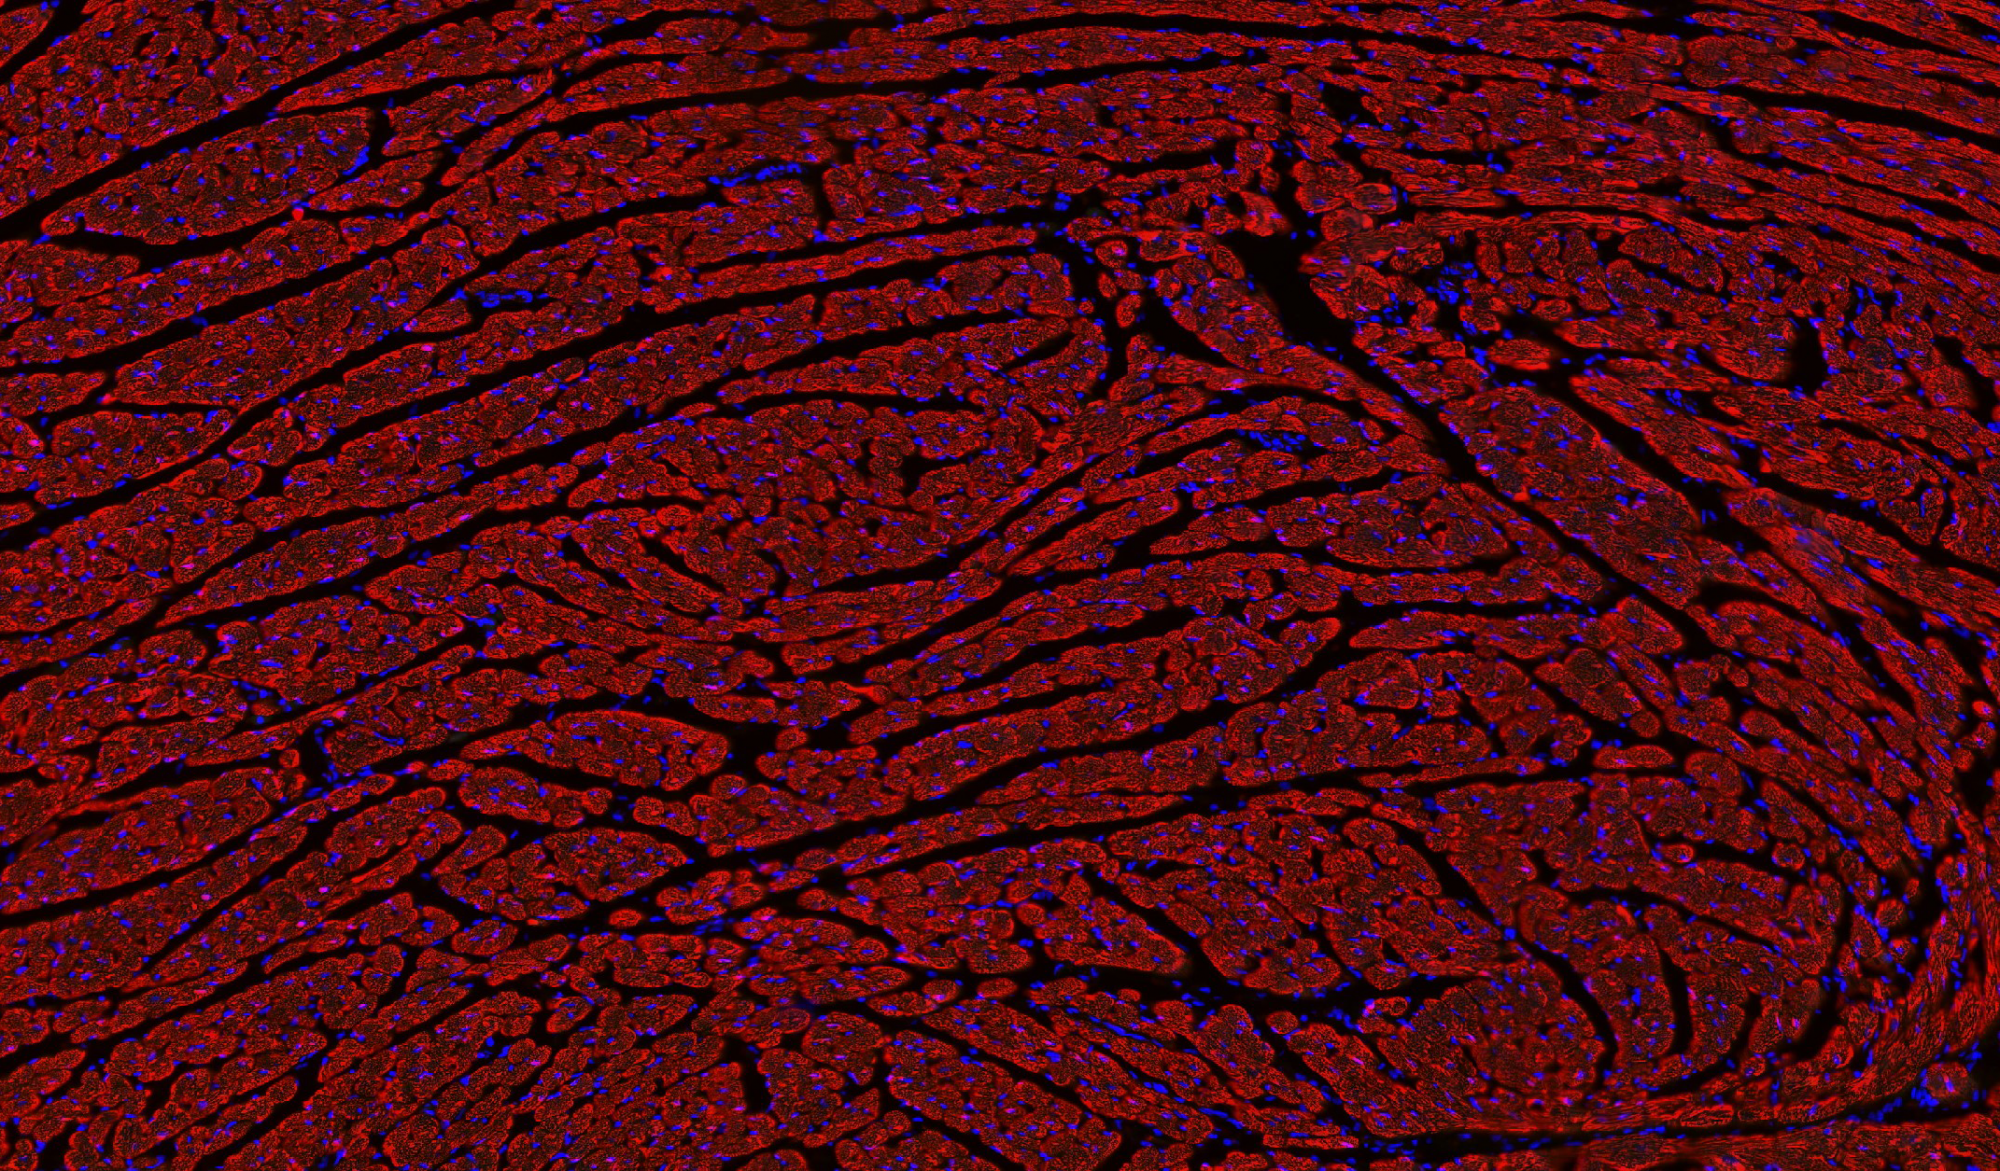

病理平臺(tái)可承接:石蠟切片,切片掃描,熒光掃描,HE染色,各種特殊染色,如:Masson、油紅O、PAS、番紅O、ALP、TRAP、甲苯胺藍(lán)以及免疫組化/熒光、原位雜交等,3D HISTECH滿足對(duì)結(jié)果高質(zhì)量,高標(biāo)準(zhǔn),周期快的實(shí)驗(yàn)外包需求,并提供染色培訓(xùn)服務(wù),分線上視頻,線下實(shí)操帶教兩種培訓(xùn)方案。

案例展示

組織染色實(shí)驗(yàn)室